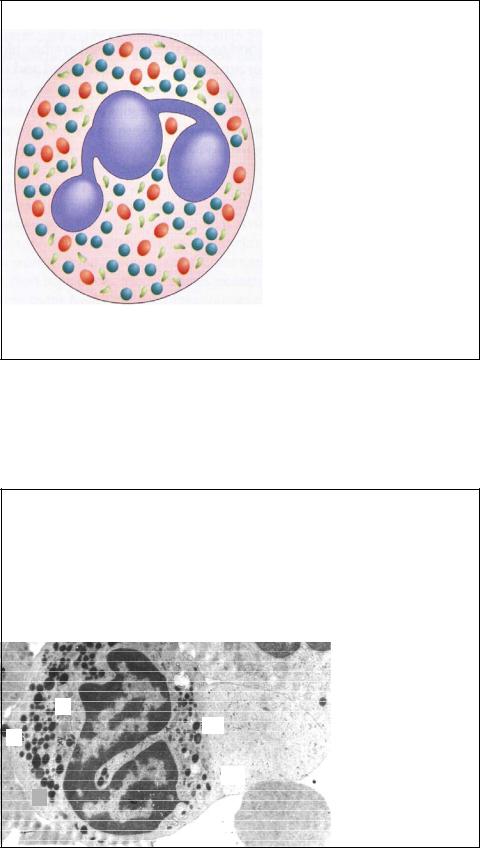

У нейтрофила 3 типа гранул: Первичные (азурофильные, показаны красным):

-аналогичны лизосомам -содержат кислые гидролазы -содержат миелопероксидазу

Вторичные гранулы (специфические, показаны синим): -специфичные для нейтрофилов -наиболее многочисленны -содержимое участвует в воспалительных реакциях

Третичные гранулы (показаны зеленым):

-содержат секретируемые ферменты (желатиназу, катепсин

D),

-могут пристраивать адгезионные

молекулы к поверхности клетки

Гранулы нейтрофила

Их всего 3 типа. Первичные (азурофильные, Ag) аналогичны лизосомам. Это первые гранулы, которые появляются в клетке во время дифференцировки, по ходу которой их число сокращается. В то время как число специфических гранул нарастает. На электронной микрофотографии они выглядят крупнее и плотнее, чем специфические (s) гранулы. Как в любых лизосомах, в азурофильных гранулах есть кислые гидролазы, но помимо этого есть много других антибактериальных агентов, таких как миелопероксидаза, эластаза и др.

Вторичные гранулы – это специфические гранулы, они в 2 раза многочисленнее, чем азурофильные. Они мельче азурофильных гранул, содержат коллагеназу IV типа, лизоцим, фагоцитин.

Ультраструктурные исследования показали, что вторичные гранулы варьируют по размерам, плотности и форме и что они содержат вещества, способствующие иммобилизации медиаторов воспаления и активации комплемента. Эти вещества секретируются во внеклеточное пространство. Третичные гранулы описаны недавно, они содержат ферменты (желатиназу, катепсин Д), способны вставлять некоторые гликопротеины в клеточные мембраны, что может способствовать клеточной адгезии и вконечном счете – фагоцитозу65.